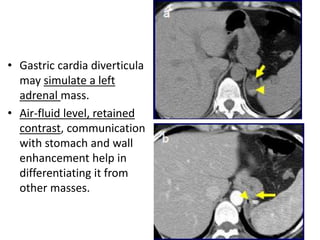

• Gastric cardia diverticula

may simulate a left

adrenal mass.

• Air-fluid level, retained

contrast, communication

with stomach and wall

enhancement help in

differentiating it from

other masses.